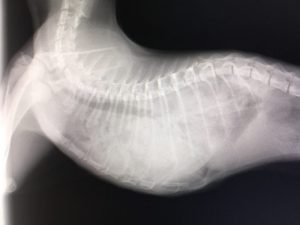

外傷性横隔膜ヘルニアの整復手術